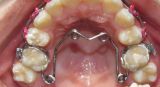

Apaprat orthodontic double-jaw

The double-jaw orthodontic device is a modern bite correction tool used to align teeth and solve various orthodontic problems.